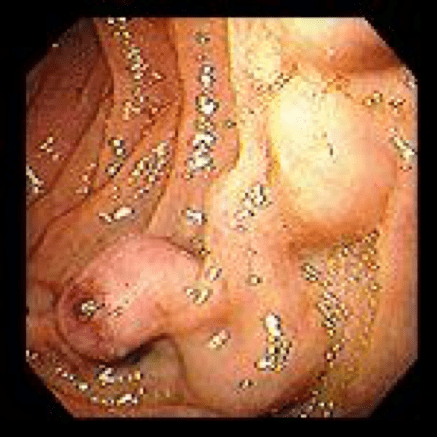

- Polyp removal